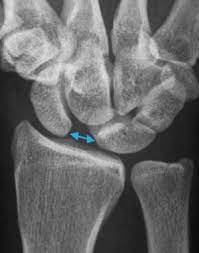

Ein gerissenes SL-Band bedeutet für das Handgelenk einen empfindlichen Stabilitätsverlust. Wie lange die Heilung eines Bänderrisses dauert hängt von der Nachbehandlung Schonung und Wundheilung ab. Wie lange ein Bänderriss am Handgelenk bis zur vollständigen Ausheilung braucht richtet sich insbesondere nach dem Schweregrad der Verletzung.